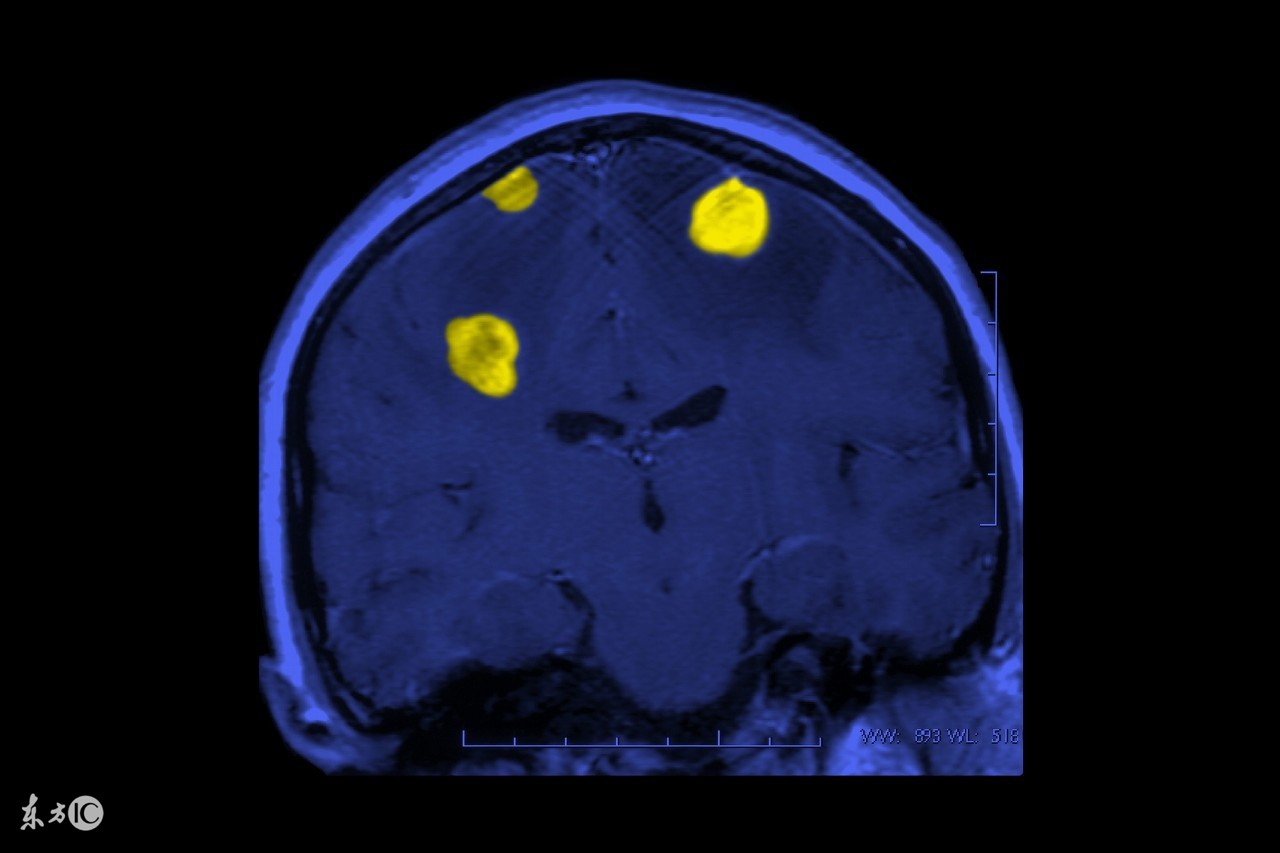

缺血缺氧性脑病这种疾病多发生在新生儿身上,缺血缺氧性脑病不仅可引起围产期新生儿死亡,而且是新生儿期以后造成伤残儿童主要原因之一,所以若是新生儿不幸患上了这种可怕的疾病,家长朋友们就要赶快为新生儿展开治疗,同时也要了解新生儿缺血缺氧性脑病的护理方法有哪些,若是大家对此不了解可以看下文中的详细介绍。

新生儿缺血缺氧性脑病主要见于有严重窒息的足月新生儿,均有明显的宫内窘迫史。由于宫内缺血缺氧影响胎儿脑细胞的能量供给。脑的能量来源和其他器官不同,几乎全部由葡萄糖氧化而来。新生儿脑的代谢最旺盛,脑的能量占全身氧能量的一半,但脑内糖原很少,而葡萄糖及氧全靠血液供给,故缺血缺氧首先影响脑的代谢。